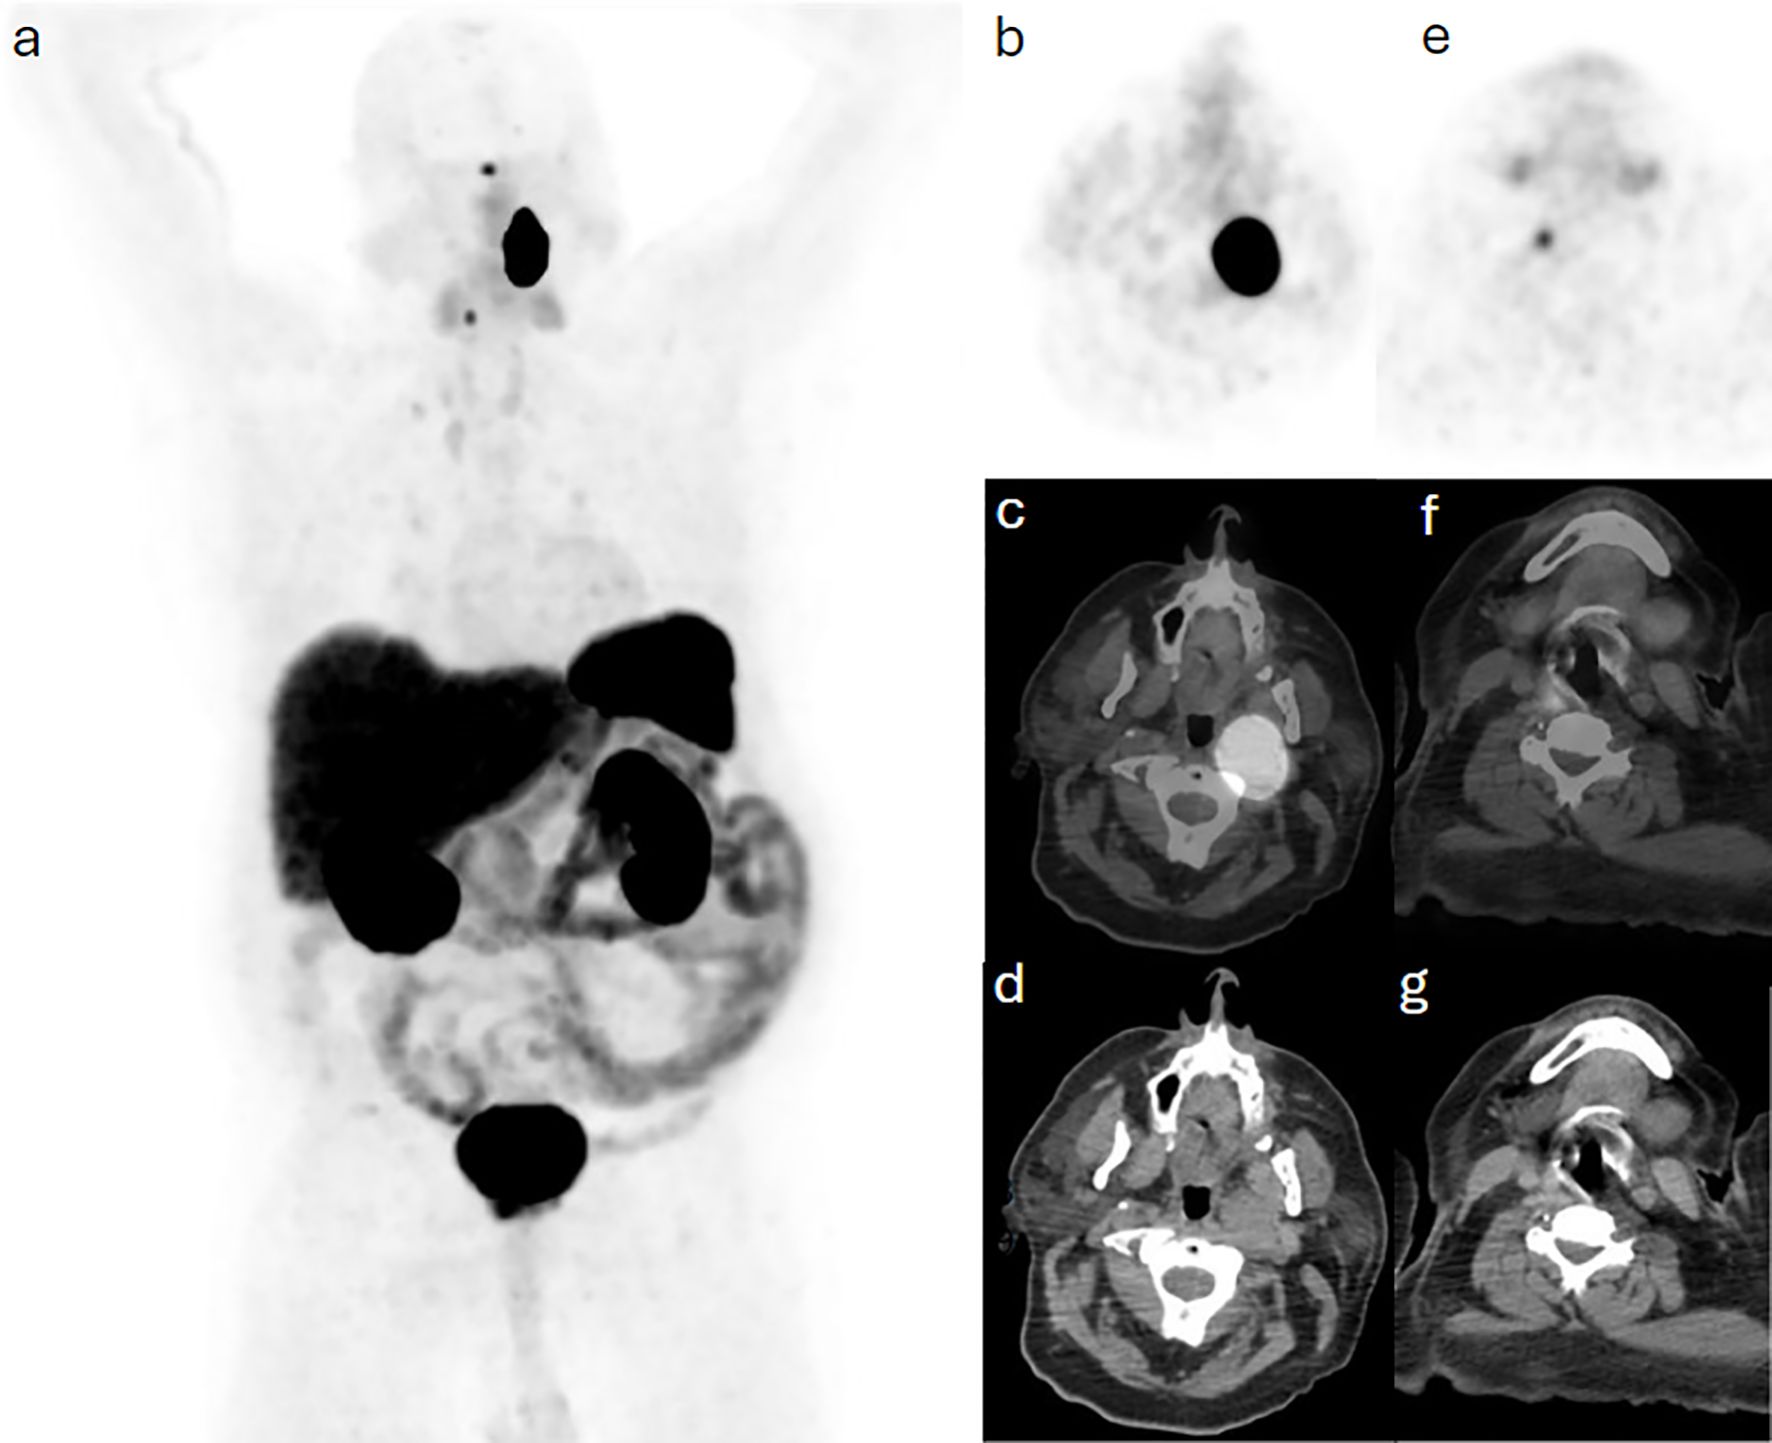

Background: Head and neck paragangliomas (HNPGs) are rare neuroendocrine tumors originating from neural crest cells, with some exhibiting malignant potential. Traditional imaging modalities, such as magnetic resonance imaging (MRI), often have limitations in detecting multifocal or metastatic disease, driving interest in more sensitive diagnostic approaches like Gallium-68 DOTATATE positron emission tomography/computed tomography (Ga-68 DOTATATE PET/CT). Methods: This retrospective study aimed to assess the effectiveness of Ga-68 DOTATATE PET/CT in the detection and management of HNPGs. Imaging data from 2015 to 2024 were reviewed, identifying four confirmed cases of HNPG. All patients underwent head and neck MRI and Ga-68 DOTATATE PET/CT scans. Data on imaging findings, treatment history, and clinical outcomes were collected and analyzed to compare the performance of Ga-68 DOTATATE PET/CT with other imaging techniques, including Iodine-123 meta-iodobenzylguanidine (I-123 MIBG) scintigraphy and Fluorine-18 fluorodeoxyglucose (F-18 FDG) PET/CT. Results: Ga-68 DOTATATE PET/CT demonstrated enhanced sensitivity in detecting both primary and metastatic lesions compared to MRI and other imaging modalities. It identified additional lesions not seen on MRI, confirmed local recurrence, and detected unsuspected metastatic sites, influencing clinical management. While Ga-68 DOTATATE PET/CT provided more diagnostic clarity than I-123 MIBG in one case, it also revealed additional metastatic sites in a patient with a succinate dehydrogenase (SDH) gene mutation, which were not detected by F-18 FDG PET/CT. Conclusion: Ga-68 DOTATATE PET/CT is a valuable imaging tool for evaluating HNPGs, with superior sensitivity in detecting both primary and metastatic lesions compared to conventional imaging. Its diagnostic advantages can significantly impact treatment planning and patient management. Integrating Ga-68 DOTATATE PET/CT into clinical guidelines for HNPG evaluation may enhance diagnostic accuracy. Further research with larger cohorts is warranted to confirm these findings and establish standardized interpretation criteria.